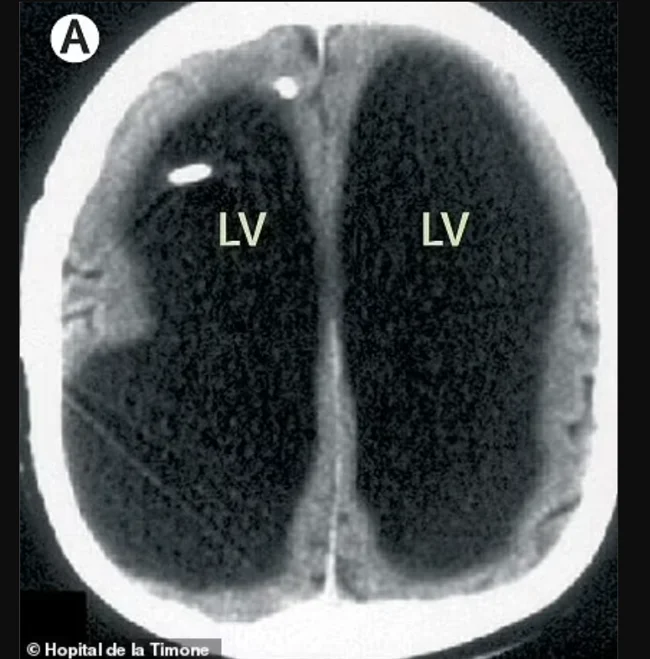

У пациента практически полностью отсутствовало мозговое вещество в черепной коробке, а остатки сжались в узкий слой и прижались к краям черепа. Оказалось, что с 14 лет в его мозге разрастался огромный карман жидкости (чёрная область на фото — жидкость), что привело к увеличению черепа.